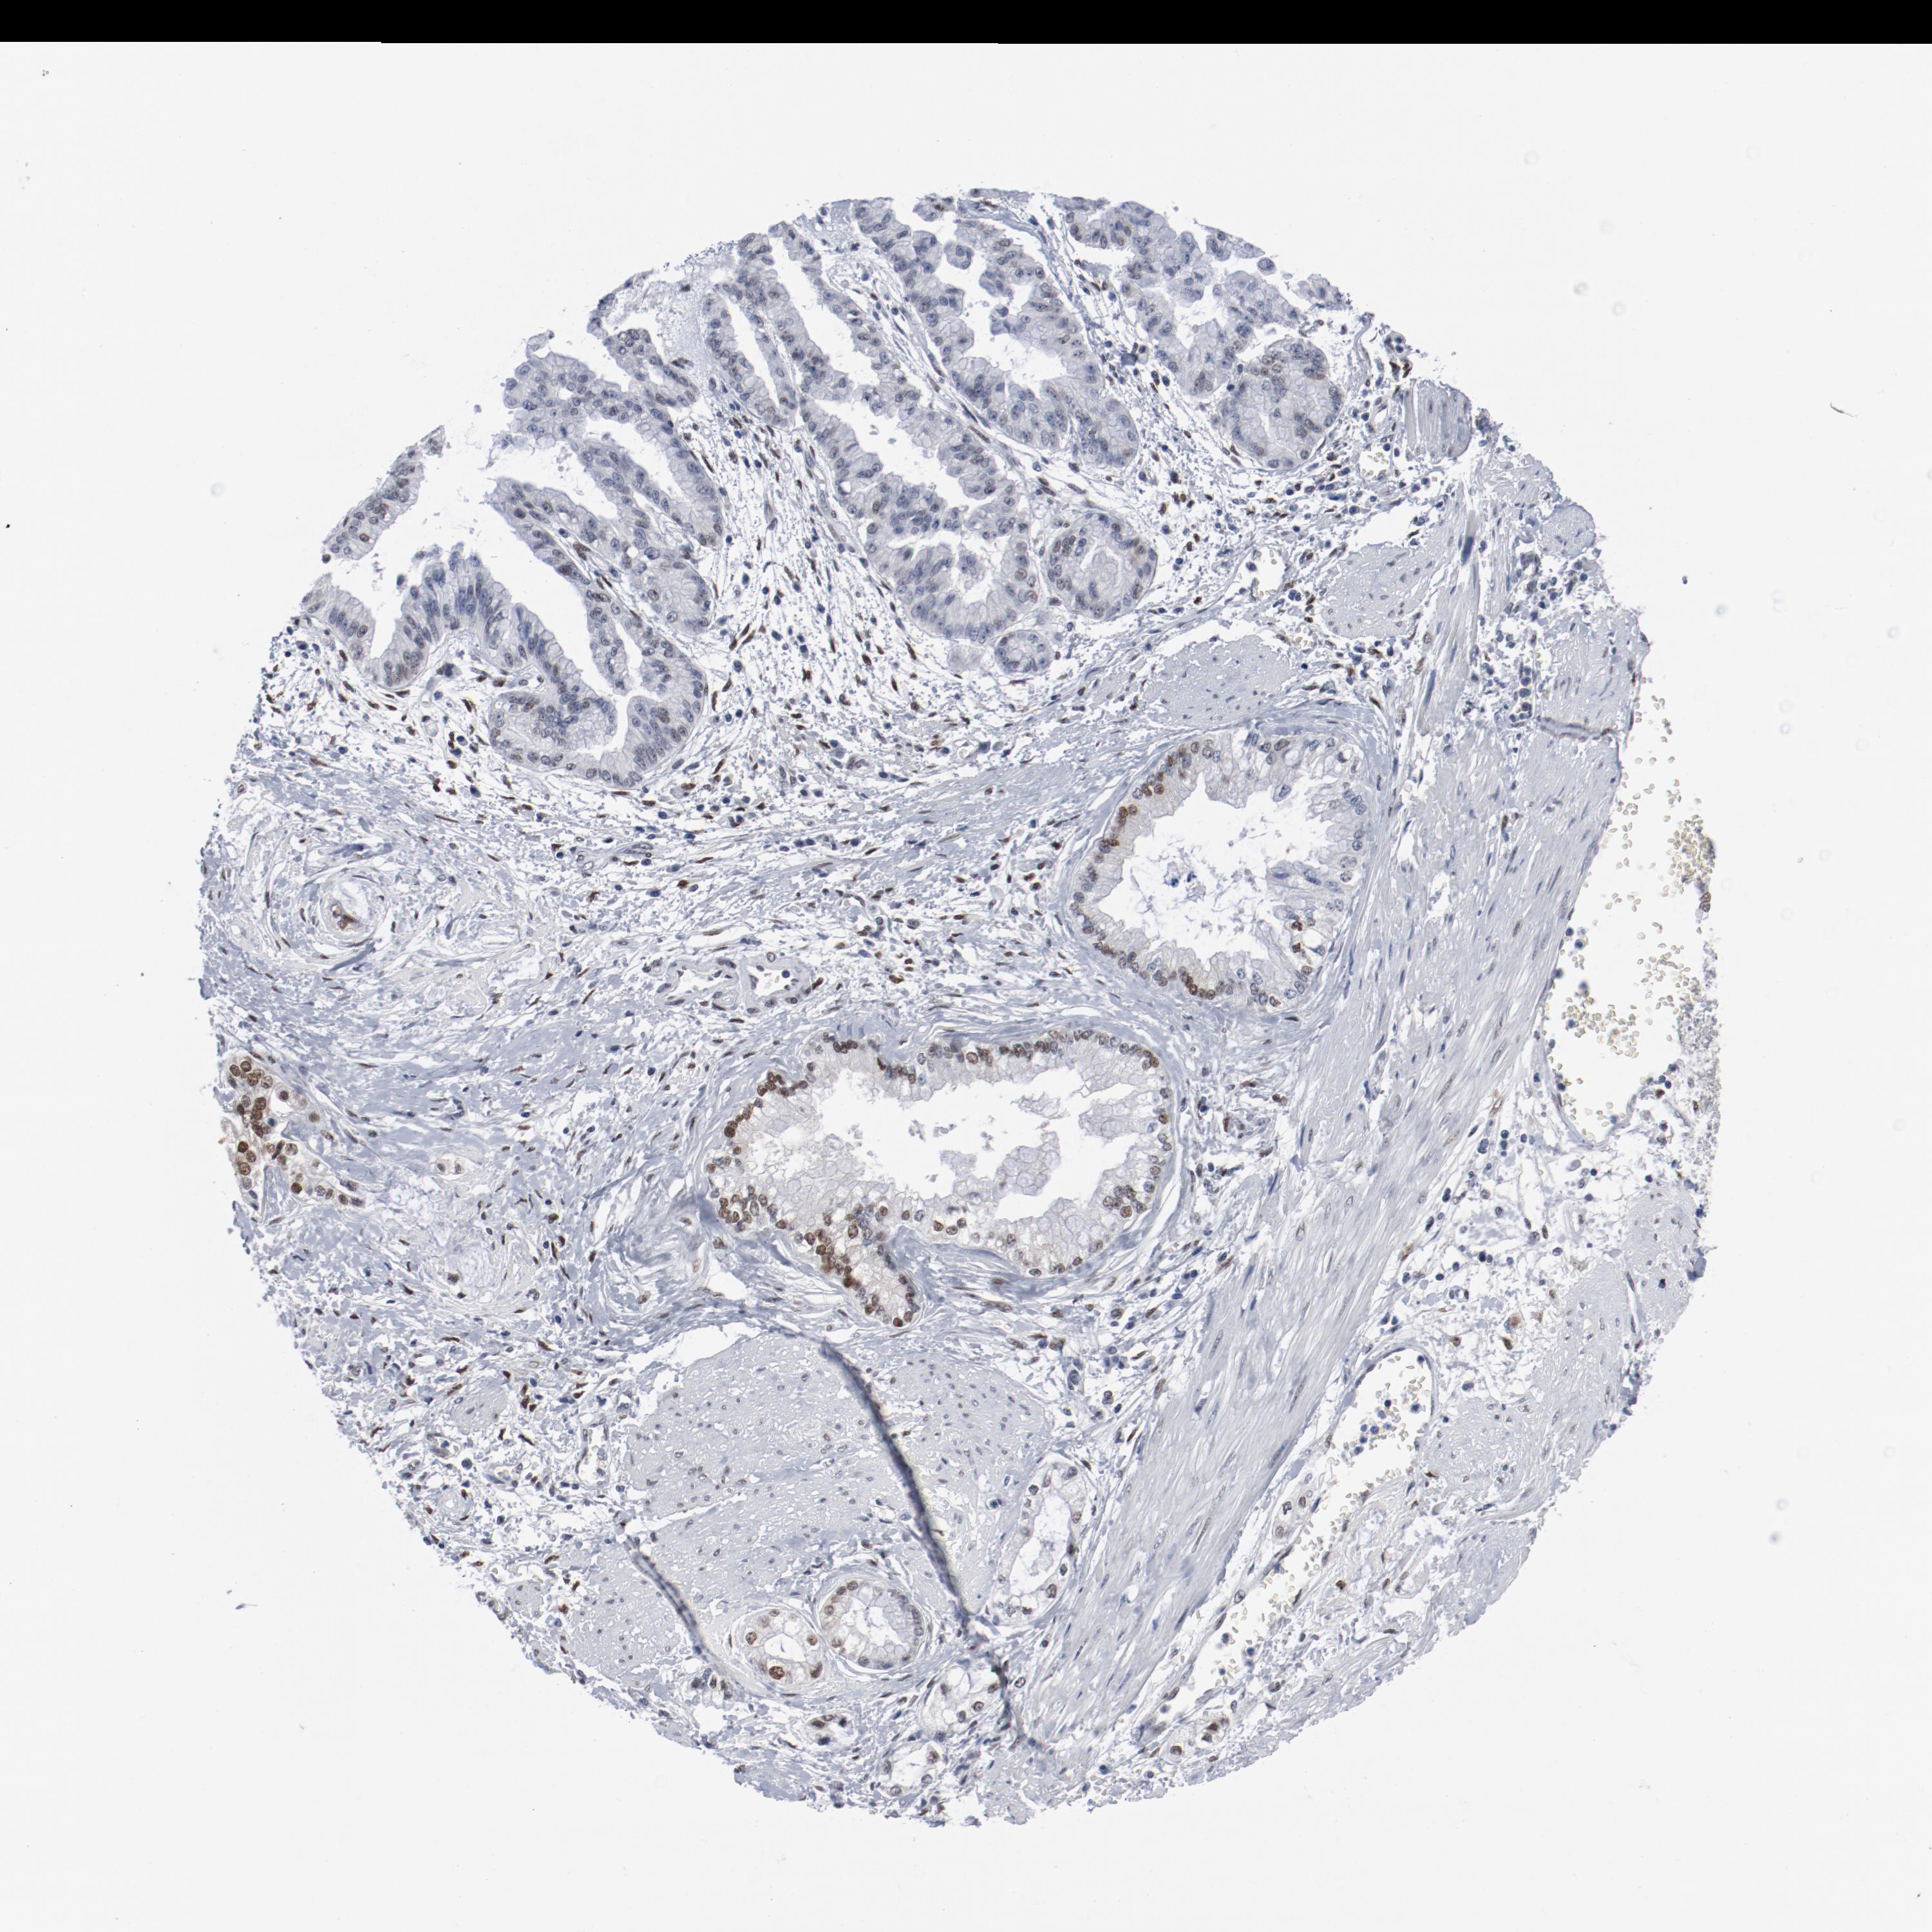

LIVER CANCER - Protein expressioni

A mouse-over function shows sample information and annotation data. Click on an image to view it in a full screen mode. Samples can be filtered based on level of antibody staining by selecting one or several of the following categories: high, medium, low and not detected. The assay and annotation is described here.

Antibody stainingi

Antibody staining in the annotated cell types in the current human tissue is reported as not detected, low, medium, or high, based on conventional immunohistochemistry profiling in selected tissues. This score is based on the combination of the staining intensity and fraction of stained cells.

Each image is clickable and will lead to virtual microscopy that enables deeper exploration of all samples and also displays staining intensity scores, fraction scores and subcellular localization as well as patient and tissue information for each sample.

Antibody CAB004318

Cholangiocarcinoma

Carcinoma, Hepatocellular, NOS